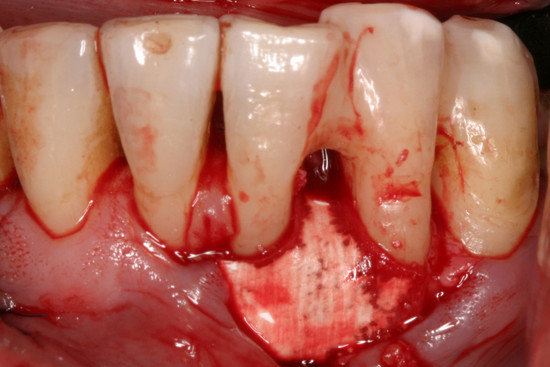

Przytwierdzanie: doskonała hydrofilność sprzyja przyleganiu Geistlich Bio-Gide® Perio do przeszczepu i otaczającej kości. Membranę można również zaszyć lub przytwierdzić pinami (dzięki uprzejmości prof. Christgau, Dusseldorf, Niemcy).